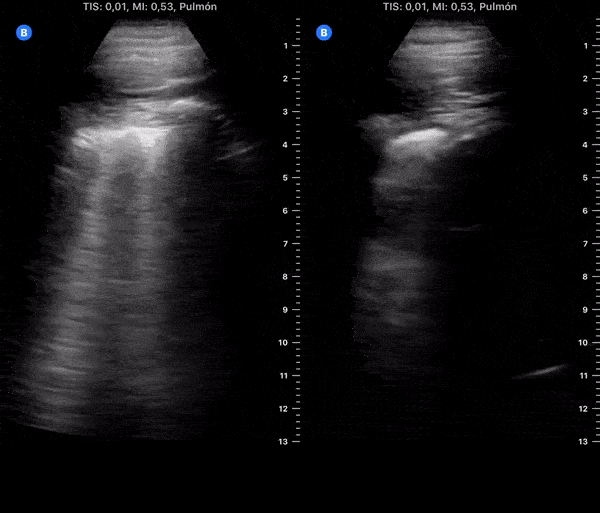

COVID 19 Lung US Disease Progression - Day 15

Day 15 after #COVID diagnosis. Similar cough, less weakness. Diarrhea due azithromycin. No fever or shortness of breath. SpO2 97%. #POCUS update: Similar to yesterday, thick pleura & bilateral scattered B-lines. @yaletung